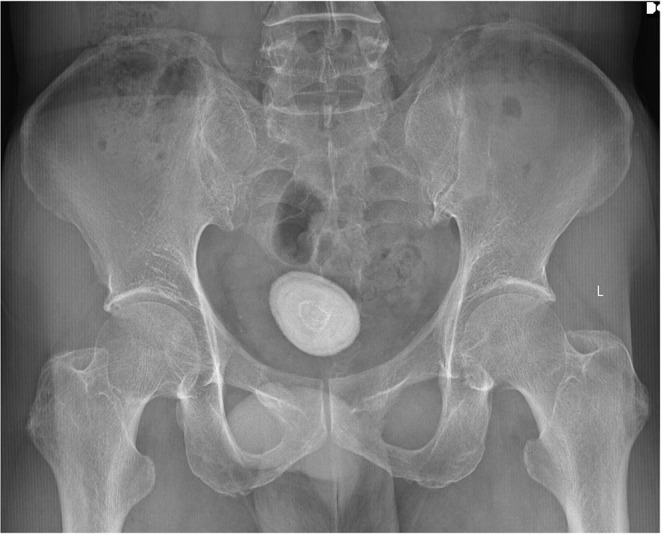

Bladder foreign bodies (BFBs) are an uncommon clinical occurrence, often resulting from trauma, self-insertion, iatrogenic causes, or organ migration. These objects can act as nidus for stone formation, leading to vesicolithiasis. Here, we present a rare case of a 61-year-old male with hematuria, dysuria, and abdominal pain. Initial evaluation, including imaging and cystoscopy, revealed a bladder stone encapsulating a foreign object identified as a blue cable wire. Despite denying self-insertion, his history suggested potential unreported trauma. Management involved cystoscopic lithotripsy and foreign body extraction. The case underscores how foreign objects act as nidus for stone formation through inflammatory and biochemical pathways, emphasizing the importance of early diagnosis and appropriate surgical management to prevent severe complications.